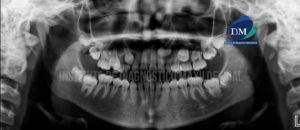

Paciente masculino de 17 años acude al Instituto de Diagnostico maxilofacial para evaluación imagenológica general. A la evaluación de la radiografía panorámica, evidenciamos que las